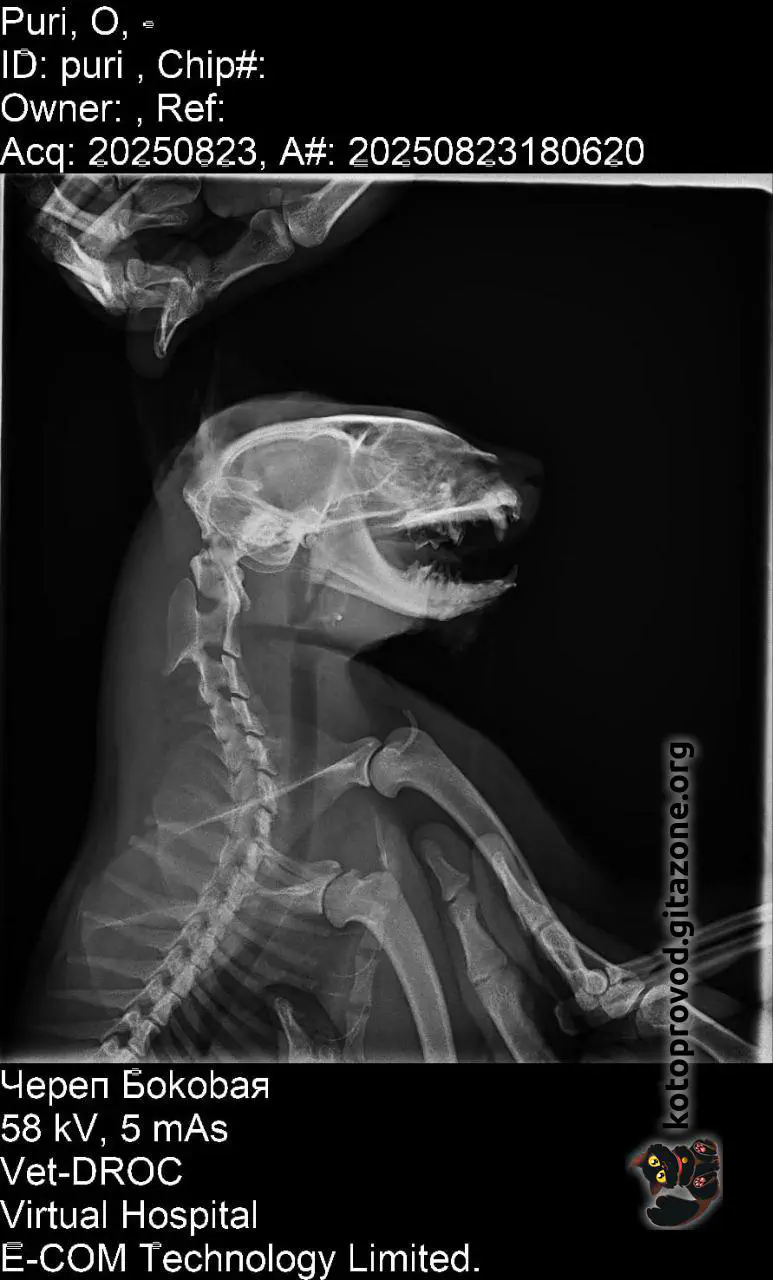

Purri was found on August 23, 2025, in very serious condition. He had injuries to his eye and jaw; the jaw had healed incorrectly after an old trauma. He required reconstructive surgery of the lower lip and eye, as well as removal of broken tooth roots and a canine that continued to injure his lip. Several surgeries and a long recovery followed.

X-ray images: